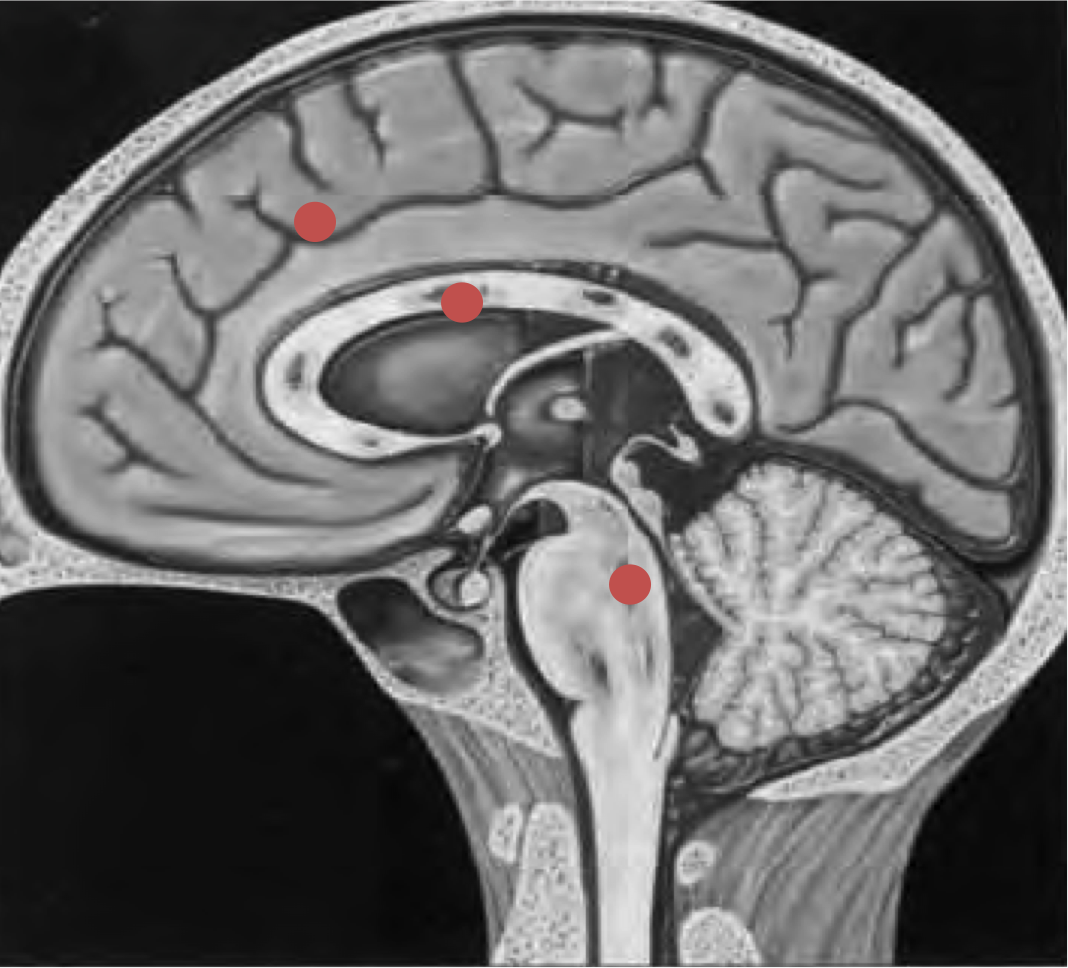

Localizaciones:

- Grado 1: Interfase cortico-subcortical (lóbulos frontales y temporales sobre todo)

- Grado 2: Grado 1 + Cuerpo calloso (en el esplenio sobre todo)

- Grado 3: grado 2 + Tronco del encéfalo.

Además la localización cortico-subcortical, el cuerpo calloso es otra localización (esplenio) y normalmente se acompaña de daño axonal difuso también en hemisferios cerebelosos y tronco del encéfalo (regiones posterolaterales de mesencéfalo y protuberancia).